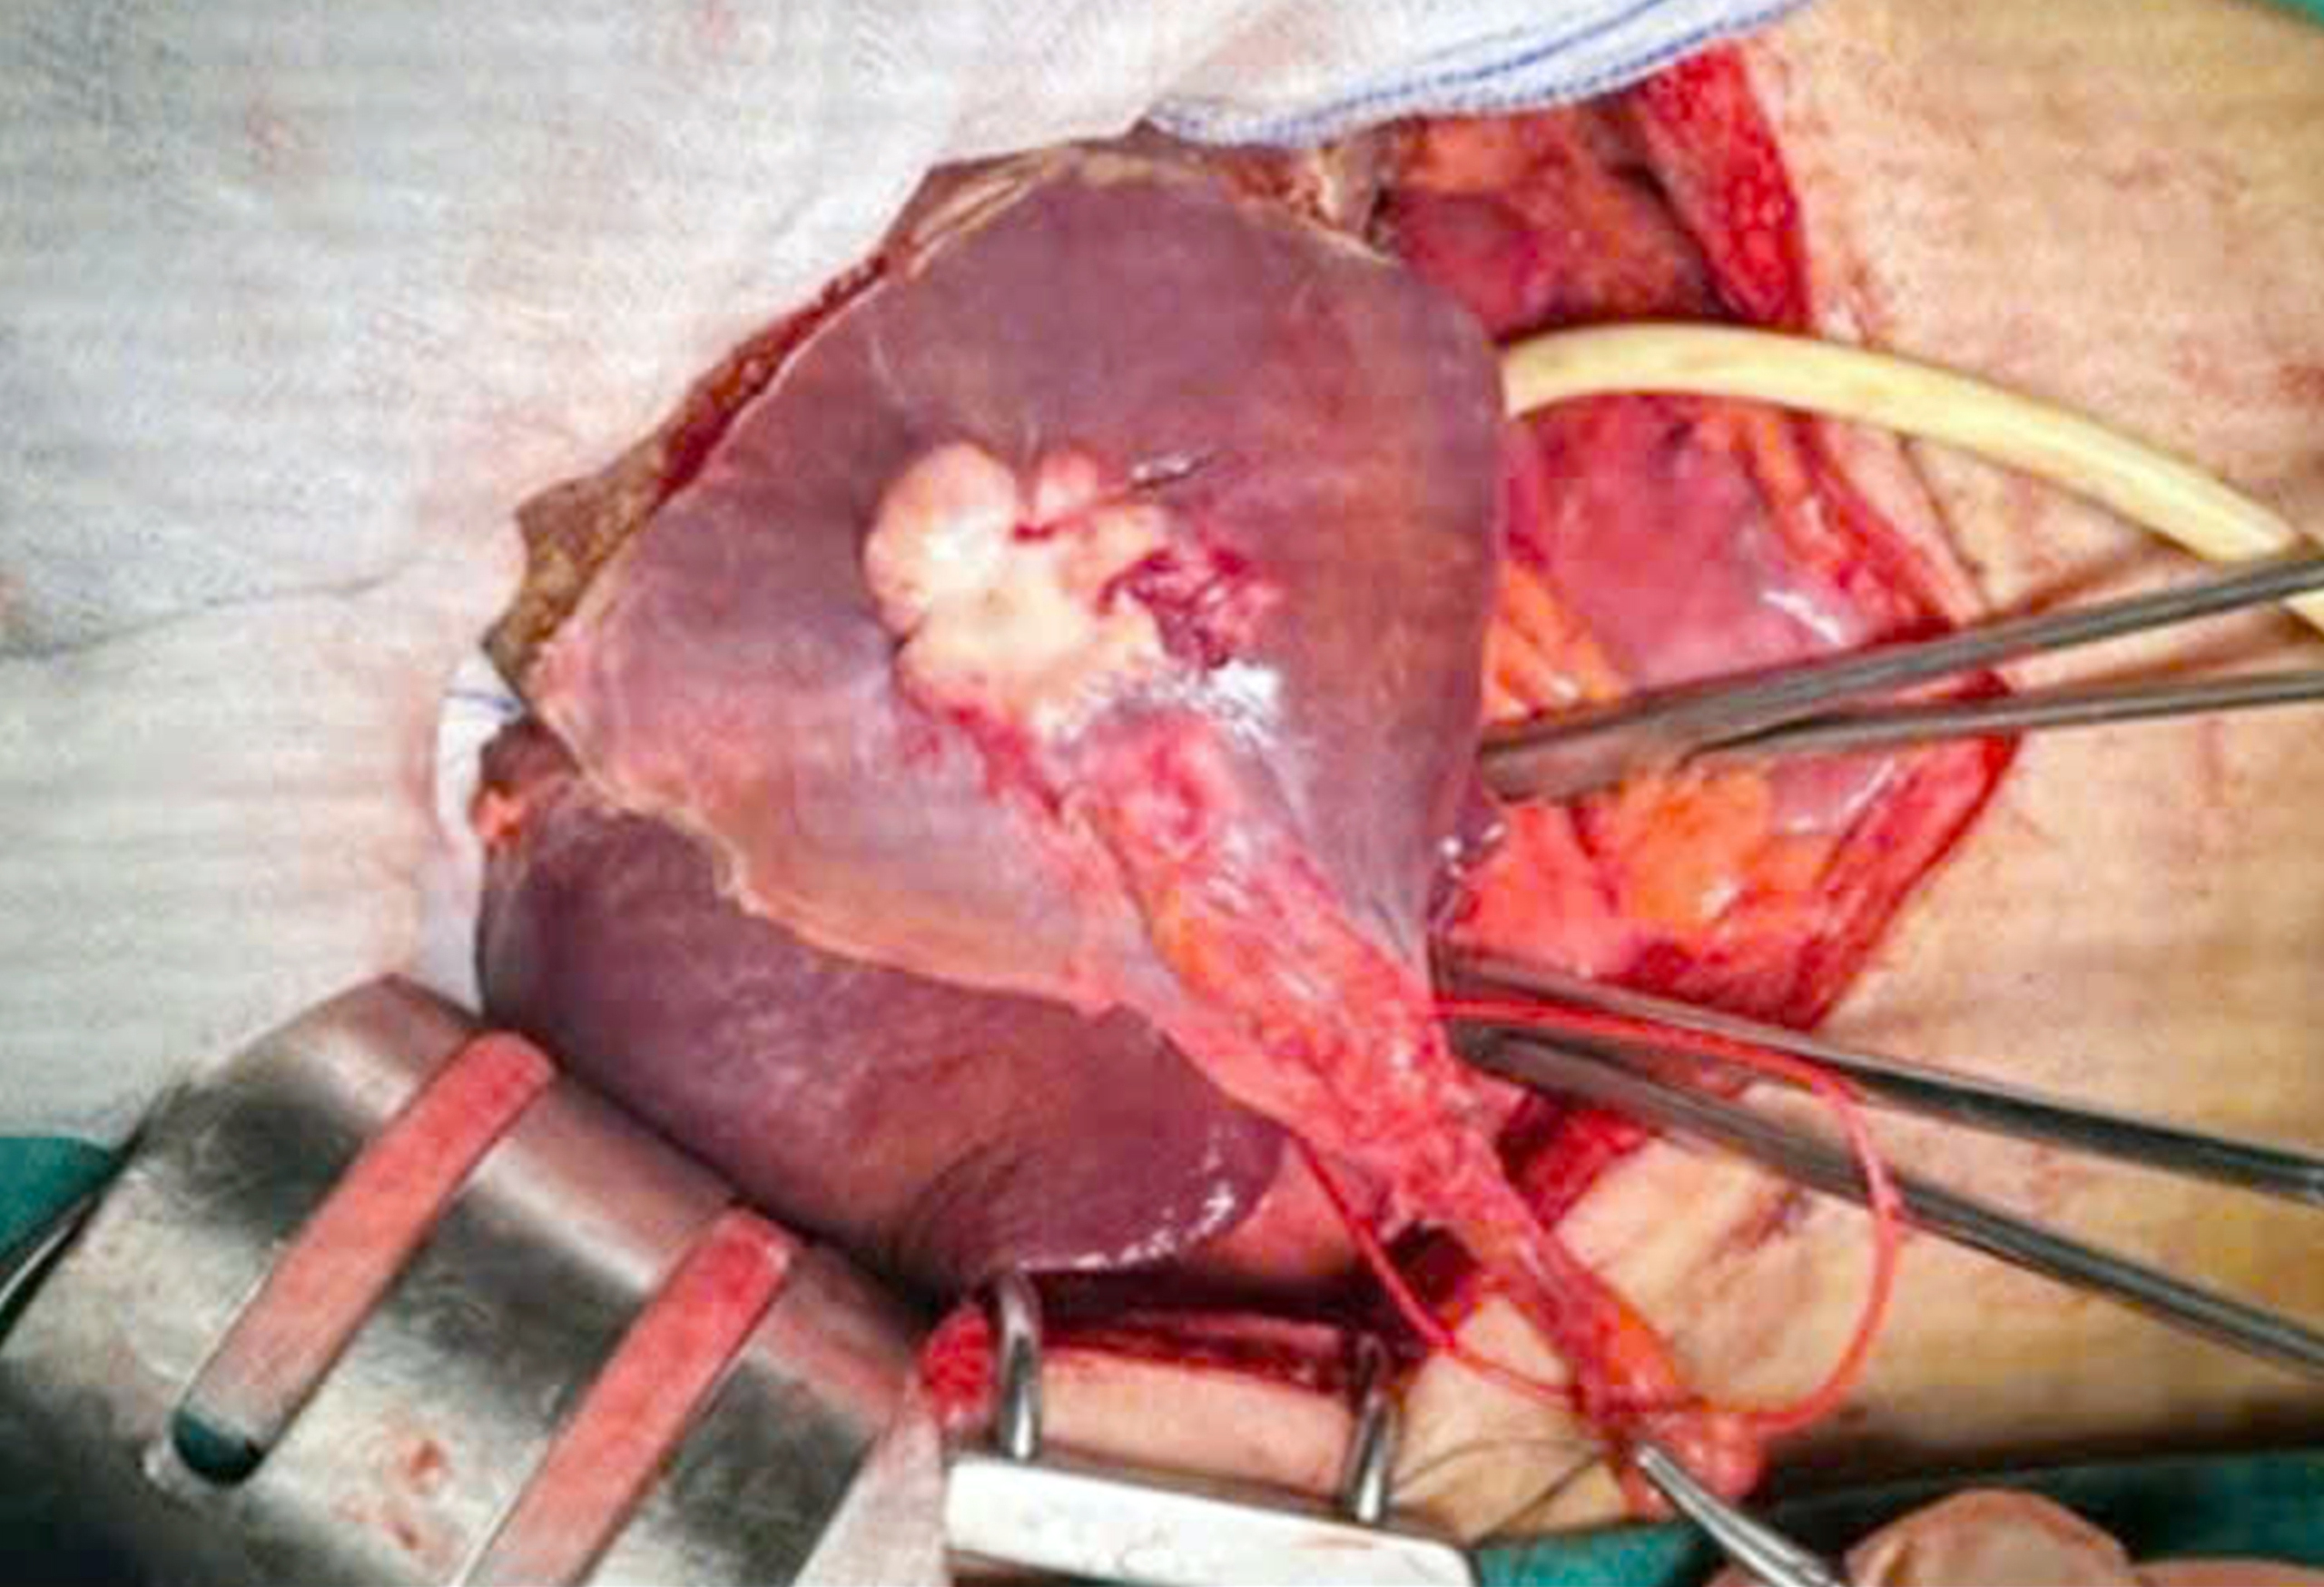

রোগীর পিত্তথলির পাথর অপসারণের জন্য অস্ত্রোপচার এবং লোবেকটমি করা হয়েছে - ছবি সৌজন্যে হাসপাতাল।

একইভাবে, মিসেস এইচটিকেএইচ (৪৭ বছর বয়সী, প্রাক্তন সোক ট্রাং প্রদেশের বাসিন্দা) বারবার পেটে ব্যথা অনুভব করেন। ভিন লং-এর জুয়েন এ জেনারেল হাসপাতালে পরীক্ষা করার পর দেখা যায় যে পিত্তথলির পাথরগুলি সাধারণ পিত্ত নালী এবং লিভারের বাম অংশে ভরে যাচ্ছে, যার ফলে বাম হেপাটিক ফাইব্রোসিস হচ্ছে। অস্ত্রোপচারের মাধ্যমে ১৪ x ৮ মিমি আকারের অসংখ্য ছোট পাথর একসাথে জমে থাকা অবস্থায় অপসারণ করা হয়েছে এবং লিভারের বাম অংশের রিসেকশন এবং পিত্ত নালীতে একটি ড্রেনেজ টিউব স্থাপন করা হয়েছে... যা কার্যকরভাবে আরও জটিলতা প্রতিরোধ করে।